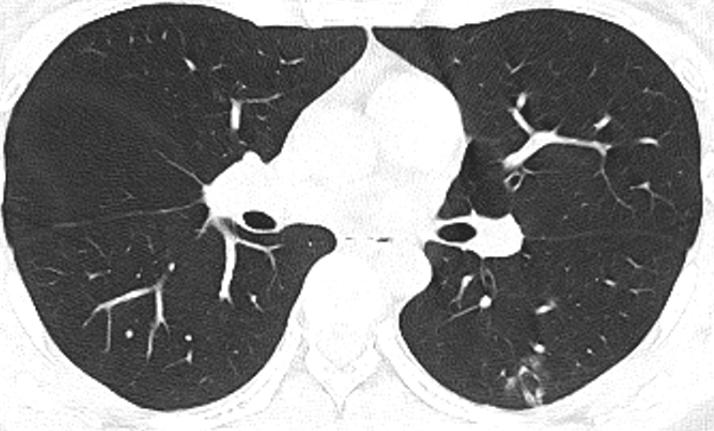

胸部CT示:双肺多发磨玻璃结节,左下叶背段散在实性结节,散在小空洞,部分支气管的管壁增厚,如下(图1~17)。